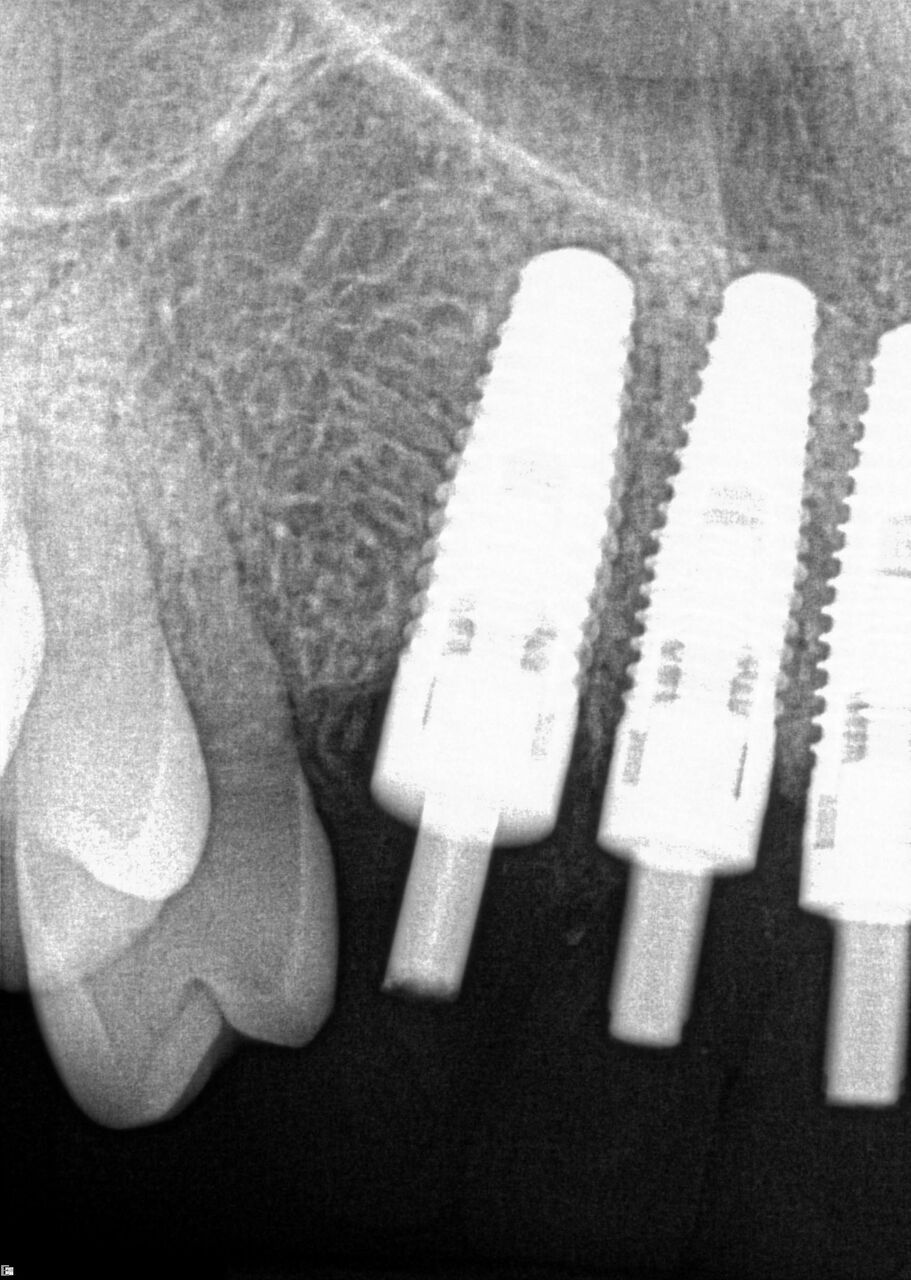

A 42-year-old man presented with a very loose bridge on Nos. 6 through 9 with periodontally compromised retainers on Nos. 6 and 9 (Figure 17 through Figure 19), and endodontically involved No. 10 with a calcified canal. Teeth Nos. 6, 9, and 10 were extracted, the sockets fully debrided, and pontic soft tissue on Nos. 7 and 8 sculpted to be symmetrical in soft tissue contour with the contralateral lateral incisor and central incisor locations. Implants were secured in position Nos. 6 through 10 (Figure 20) in excess of 45 Ncm, the bone was milled to provide unimpeded seating of temporary abutments, and temporary crowns were fabricated chairside and adjusted to be out of occlusion in centric relation and all excursions. The temporary crowns were cemented after extrusion of excess cement extraorally and the patient was prescribed antibiotics, analgesics, and instructed in postoperative care particular to immediately provisionally restored implants. At 6 months, integration was confirmed (Figure 20 through Figure 23) and after placement of scanning abutments, the implants and soft tissues were scanned. Final crowns were fabricated from the scanned images and were cemented after extrusion of excess cement extraorally (Figure 24 through Figure 26), and oral hygiene procedures were reviewed.

(17.) Case 3 initial radiograph of bridge on Nos. 6 through 9 and crown on No. 10.

Figure 17

(18.) Case 3 initial radiograph of bridge on Nos. 6 through 9 and crown on No. 10.

Figure 18

(19.) Initial clinical evaluation of Nos. 6 through 9 bridge and crown on No. 10.

Figure 19